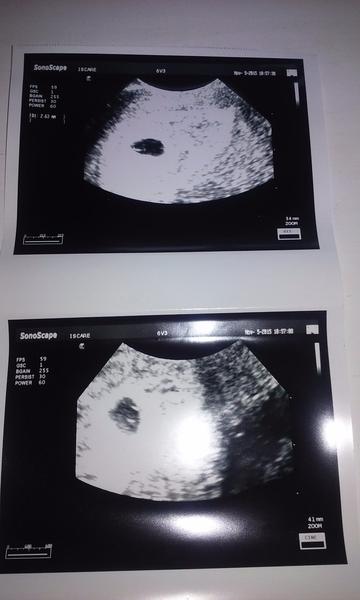

@sydnyi11 ja viem, citala som, ze to je normalne. Ale som paranoidna a zakazdym si myslim, ze to uz idu kramy. To su tie skusenosti s 2 chemickymi... Este 10 dni do sona a az potom uverim, ze je vsetko OK 😕